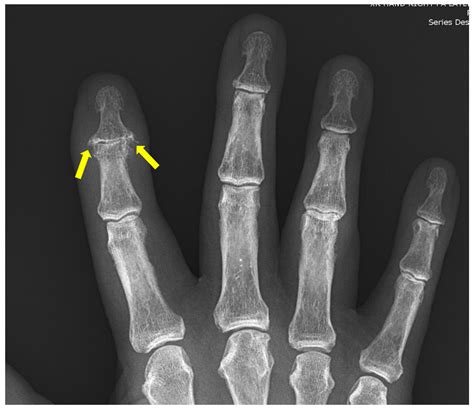

2. Imaging Tests: X-rays are the standard tool to look for cartilage loss, bone spurs, and joint space narrowing. MRI or ultrasound may be used for a more detailed look at soft tissues.

• pictures of arthritis in fingers

• arthritis in hands pictures